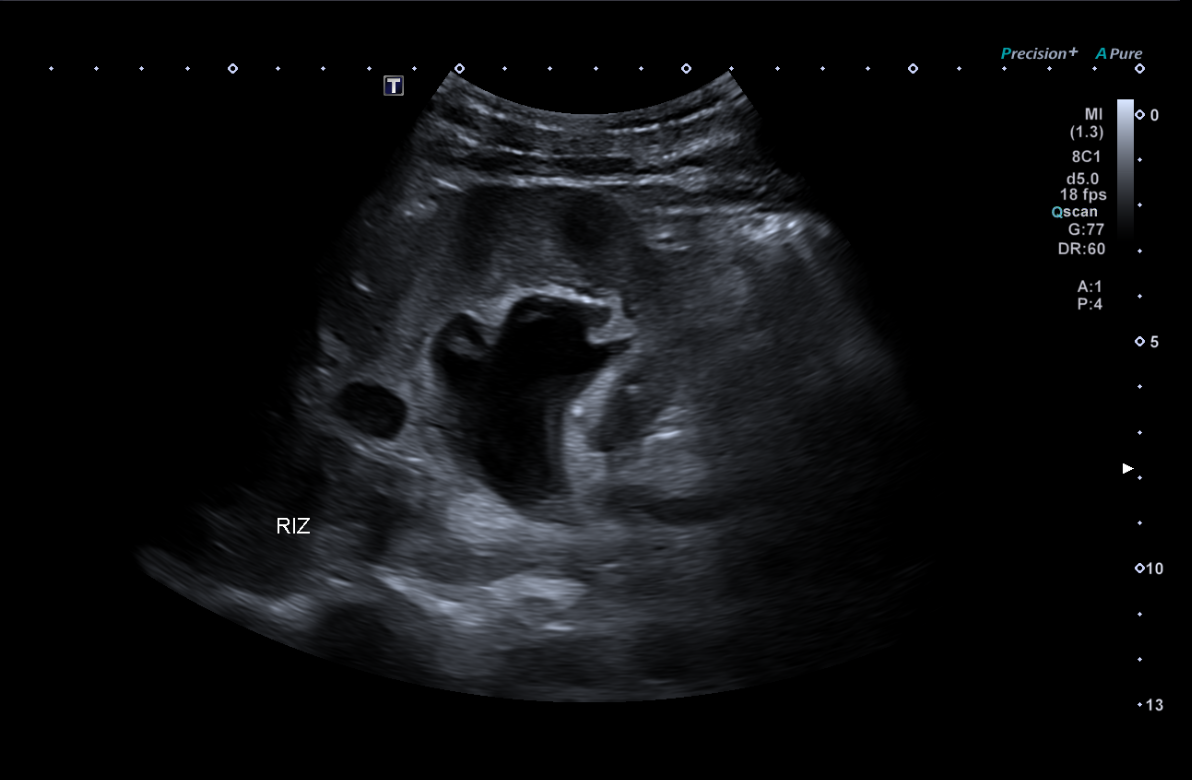

Se establece como hipótesis diagnóstica hidronefrosis. Se plantea como diagnóstico diferencial posible cistitis ulcerativa, así como uropatía obstructiva secundaria a consumo de ketamina. La ecografía clínica resulta determinante para la confirmación diagnóstica, evidenciando datos compatibles con obstrucción de la vía urinaria.

En vista del deterioro de la función renal del paciente, se decide ingreso hospitalario en medicina interna. Se realiza ecografía renal reglada por radiología la mañana siguiente, encontrando hidronefrosis grado III-IV bilateral.